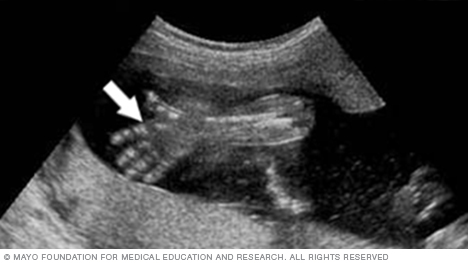

Open hand and fingers, as shown below, are among the signs that a health care team looks for on an ultrasound to confirm that a fetus is growing and developing as expected.